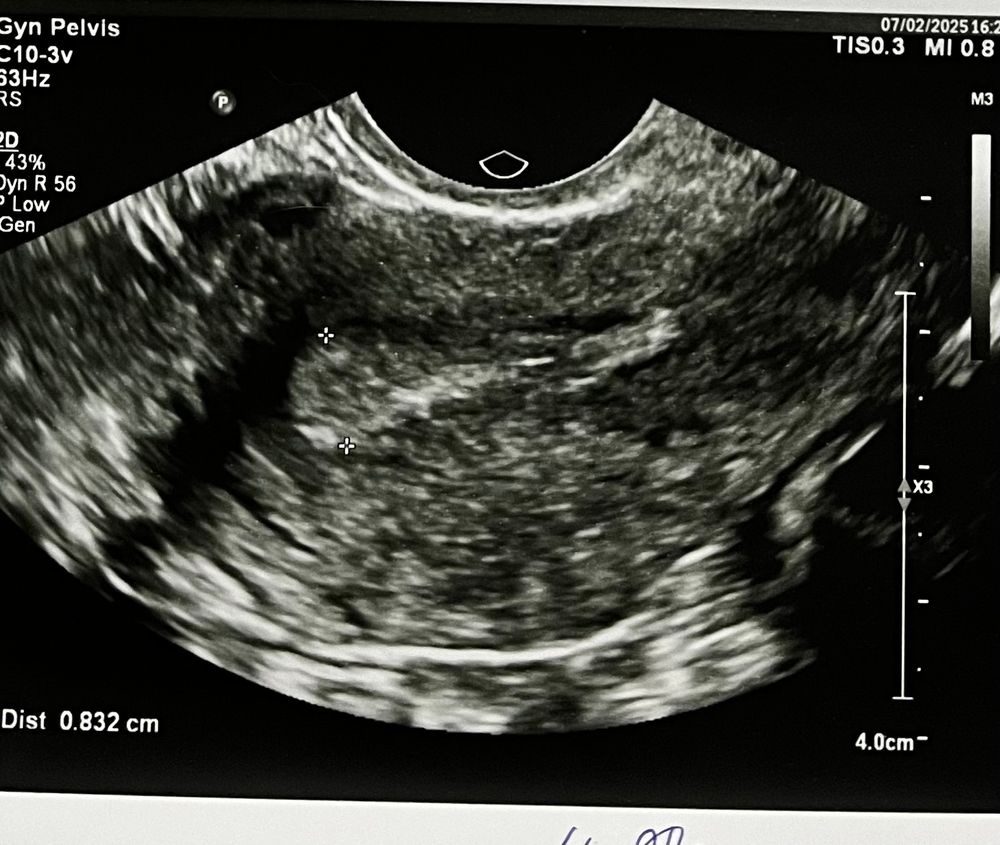

Последние кд были с 09.01.2025 по 14.01.2025, цикл 27-28 дней. Овуляция по приложению должна была быть 23.01.2025(15 дц), и если память не изменяет, то показалось, что овуляция была на 13-14 дц. ПА был 21.01.2025. По ощущениям чувствовала себя прекрасно(что очень странно. Обычно что-нибудь да беспокоит). Было всё хорошо до 25.01.2025.. с утра началась сильная тошнота, которая длилась по 27.01.2025. День цикла сегодня 30(2 день задержки). Днем(07.02.25.) была на узи, ничего по поводу Б не сказали(снимок прикладываю). Эндометрий 8,3 мм(вроде как перед месячными он должен быть не больше 4 мм). Сделала этим же вечером тест(знаю, что нужно утром) такое ощущение, что что-то виднеется, но заметила только на фото(фото со вспышкой без фильтров).

Может кто-то разбирается в снимках узи, да подскажет что-нибудь?🤷🏼♀️